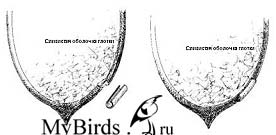

• Гортань белая или серая, а не розовая

С клинической точки зрения доминантными являются изменения в гортани (беловатые или коричневатые пятна, налет или корки, слизистые нити, сладкий запах и т.д.), дыхательные шумы или затрудненность дыхания.

Гортань черных стрижей, которой никогда не уделялось внимания, обычно стерильна. «Предварительно обработанные» стрижи, однако, часто демонстрируют широкий спектр микробов, являющихся факультативно болезнетворными. Среди прочих встречаются синегнойная палочка, протеи, E coli, клебсиелла, гемолизирующая кишечная палочка, золотистый стафилококк. Часто эти патогенные микроорганизмы соседствуют с грибами Candida ablicans. Кандидоз у стрижей хорошо поддается лечению Флюконазолом, хотя он токсичен для печени, поэтому предпочтение отдается обработке Нистатином (воздействует местно, должен контактировать с дрожжами).

Для успешного лечения необходимо бактериальное и микологическое исследование мазка из гортани, а также спектра действия антибиотика. У диких птиц наблюдается повышение резистентности к распространенным антибиотикам.

Для фиксации простого перелома подклювья в качестве шины можно воспользоваться небольшим кусочком стержня пера, например, голубиного, которое разрезается по длине и, если необходимо, надевается поверх перелома как ползун, а затем оставляется на несколько дней. Достигаемая таким способом стабильность вполне удовлетворительна. Для наблюдаемых случаев воспаления слизистой оболочки глотки в месте наложения шины отсутствовали, но это необходимо тщательно отслеживать.